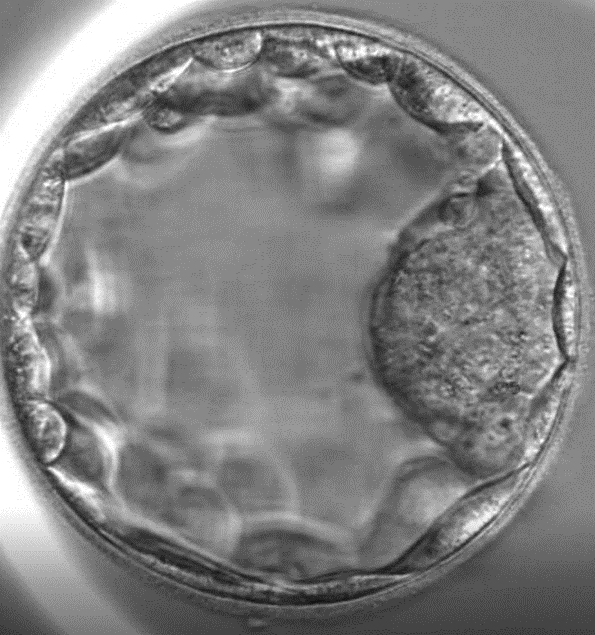

5 day blastocyst ready to implant into a womb (not my actual one)

I woke up a few hours later in a daze, with discomfort in my nether region.  It was painful to sit upright.  For the procedure they inserted a device up my canal, punctured the wall of my uterus, to access the ovaries for the eggs.  They extracted 7 eggs, of which 5 were viable.  They inseminated all of them with my friend's sperm.  By day 5, only 2 blastocysts made it.  This is quite normal, though I heard that some donors can produce 20+ eggs from the ovaries, which will increase the chance of viable embryos.